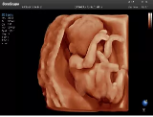

4容積探頭

積探頭是在二維圖像的基礎(chǔ)上,將連續(xù)采集的空間分布位置,經(jīng)過計(jì)算機(jī)重建算法,從而獲得完整的空間形態(tài)。

適用于:胎兒面部、脊柱和肢體等。

優(yōu)勢(shì)特點(diǎn):快速獲取、掃查連續(xù)均勻、解剖結(jié)構(gòu)顯示為容積數(shù)據(jù)、準(zhǔn)確進(jìn)行容積測(cè)量。